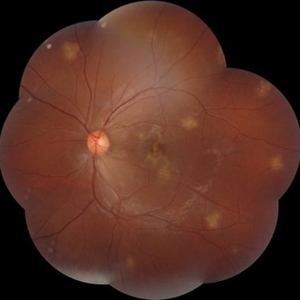

Fundus examination of a 35-year-old man with focal areas of altered retinal pigment epithelium and subretinal yellowish lesion in the foveal area in the right eye. Left eye showed a punched out circumscribed lesion in the center of the macula with thin foveal roof suggestive probably of the internal limiting membrane. Macular coloboma is characterized by a sharply defined, oval or rounded, usually unilateral, atrophic lesions of varying size presenting rudimentary or absent retina, choroid and sclera located at the macula leading to decreased vision in the central area of the fundus. It can be associated with retinal dystrophy in the fellow eye, as was the case in our patient.

Photographer: Priyanshi Kambodi, RNC Eye Hospital, Valsad

Condition/keywords: macular coloboma